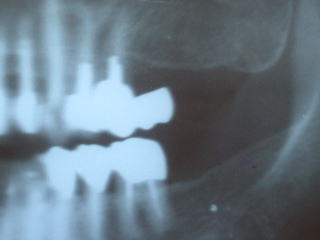

下の奥歯の例です。